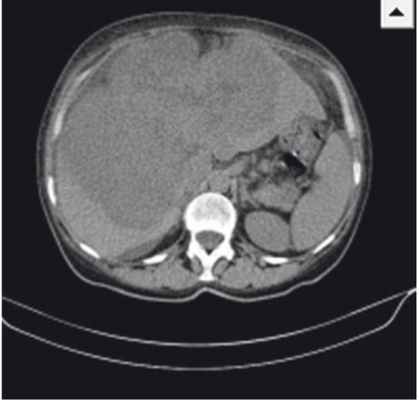

Результаты контрольной КТ от 12.05.2014: печень увеличена в размерах, деформирована, имеет крупнобугристый контур; паренхима обеих долей печени субтотально (около 70%) заменена объемным мультифокусным образованием размерами 208 × 127 × 185 мм (рост) с неровными бугристыми контурами и неоднородной гиподенсной плотности (рис.). При проведении ангиографии обнаружено, что образование активно, выраженно неравномерно, преимущественно по периферии, накапливает контрастное вещество до +130 HU с сохранением зон отсутствия контрастирования (некрозы).

Рис. Компьютерно-томографическая картина гигантской цистаденокарциномы печени. Фото авторов